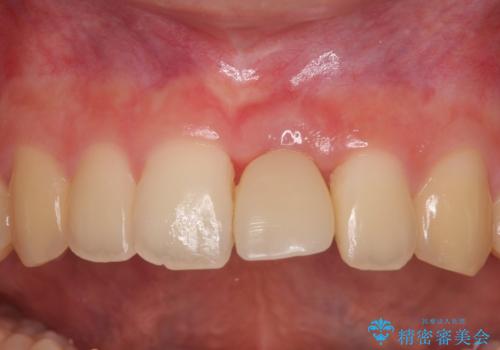

歯根吸収した前歯 短期間でのインプラント治療

- 前歯のインプラント治療を希望して来院された患者様です。

小学生の時に前歯を殴打したとのことで、歯根が吸収してしまい、抜歯が必要と判断されました。

長い間歯肉が炎症を患っていたため、炎症改善後には歯肉がやや退縮した状態となっていました。

歯肉移植により歯肉形態を改善するプランも提案しましたが、十分な仕上がりとのことで、大変満足していただけました。